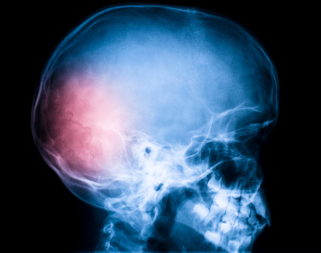

Dr. Turab Syed is a fellowship-trained orthopaedic surgeon who specialises in elective lower limb surgery and general trauma. He has fellowship training in Foot and Ankle surgery, Hip and Knee Arthroplasty, Sports Surgery as well as Trauma.

Mr. Syed offers comprehensive foot and ankle care including the most advanced and effective surgical and nonsurgical interventions. He also performs state-of-the art minimally invasive surgery and hip and knee replacement surgery.